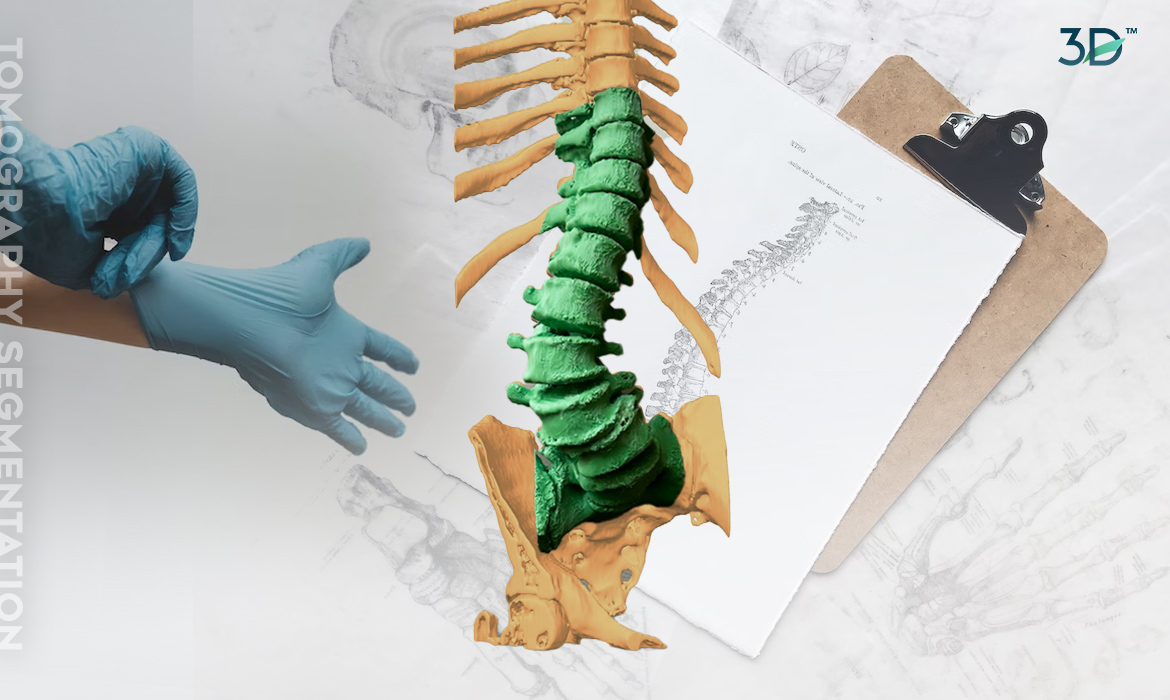

El punto de partida fue la traducción de imágenes médicas mediante la segmentación de una tomografía, lo que permitió la creación de un biomodelo 3D. Sin embargo, no bastaba con tener una réplica tridimensional; era esencial conservar los detalles anatómicos propios de la columna. Por ello, se llevó a cabo una retopología, garantizando la precisión y fidelidad del modelo. Una vez obtenido el biomodelo 3D con los detalles anatómicos adecuados, se procedió a dividir específicamente la sección de la columna que se requería imprimir. Esta sección abarcaba las áreas afectadas por la escoliosis degenerativa del adulto. Una comprensión estereoscópica a gran escala de la patología permite una planificación y una simulación más detalladas del procedimiento.